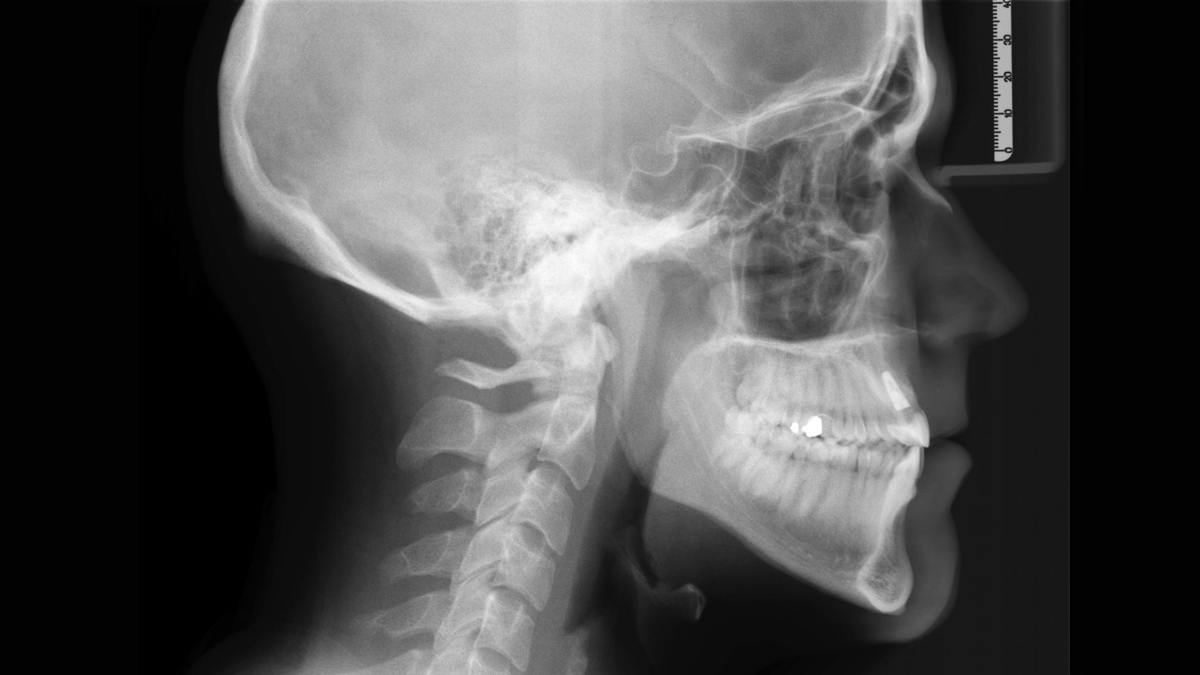

L’unité de radiographie 2D permet de s’immerger facilement dans le monde de l’imagerie numérique. Grâce à la technologie de capteur CsI et à son interface simple, vous bénéficiez de diagnostics fiables à chaque fois. L’option céphalométrique fait également de l’Orthophos E un partenaire fiable pour l’orthodontie. Dotez votre cabinet d’une large gamme de services qui ne sont possibles qu'avec l'imagerie numérique.

Pour un soutien diagnostique optimal en orthodontie, un bras céphalo à gauche peut être commandé ou installé à tout moment